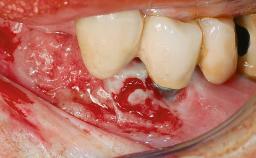

Peripheral Giant-cell Granuloma Associated with Peri-implant Tissues

Giant-cell granulomas (GCG) of the jaws are benign reactive lesions of unknown etiology, unrelated to giant-cell tumors (osteoclastomas), which are defined as benign but locally destructive and aggressive neoplasms (Jundt and coworkers 2005). Depending on their localization at the initial diagnosis, GCG are dived into central (CGCG) and peripheral (PGCG) types. CGCGs occur within the jawbones and appear as unilocular or multilocular radiolucent lesions. The incidence in the general population is very low. They are more commonly found in the mandible, mainly in children and young adults—patients are generally younger than 30 years—and have a greater incidence in females (Heithersay and coworkers 2002). The clinical behavior of CGCGs varies from slowly growing asymptomatic swellings to aggressive lesions that may result in pain, cortical perforation of the affected jaw site, and root resorption (de Lange and coworkers 2007).